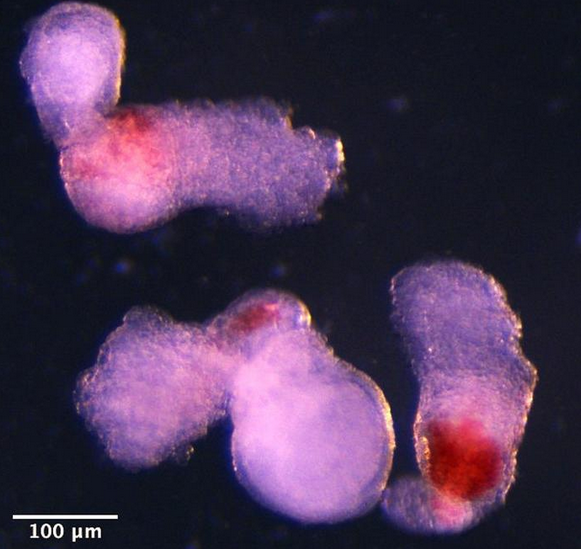

科學(xué)家用人類干細(xì)胞構(gòu)建出“類血細(xì)胞”

人類皮膚細(xì)胞育成功能性卵子